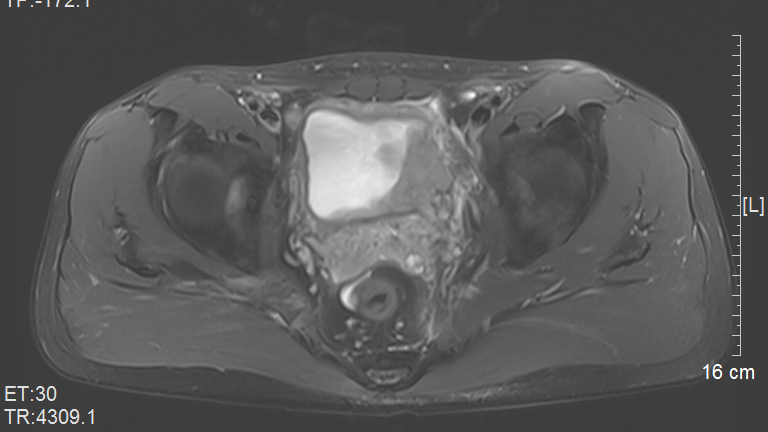

随后他接受了目前功能分子影像诊断设备PET/MR检查,复查结果显示:“膀胱治疗后改变,左侧膀胱壁稍增厚,未见肿瘤残留迹象”——这也意味着,曾先生的膀胱肿瘤很可能“奇迹”般地消失了!

▲治疗后肿瘤情况